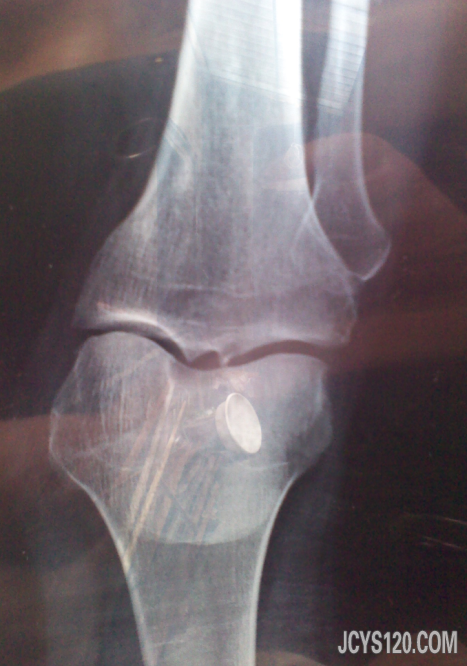

女,63岁,左小腿疼痛二十天,活动后加剧。 左小腿承山穴处有压痛,余未见明显异常。临床诊为“左坐骨神经痛”。处理有效,但是反复发作。后嘱患者膝X片,如下 由于是手机所拍,不知版主能看清不。 请 ... 阅读全文>